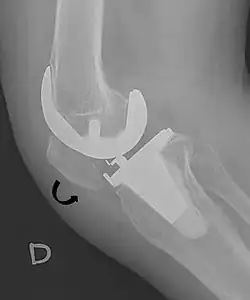

The Insall-Salvati ratio helps to indicate patella baja on lateral X-rays, and is calculated as the patellar tendon length divided by the patellar bone length. An Insall-Salvati ratio of < 0.8 indicates patella baja.[7]

- ^ Melloni, Pietro; Veintemillas, Maite; Marin, Anna; Valls, Rafael (2013). "Imaging Patellar Complications After Knee Arthroplasty". Arthroplasty - Update. doi:10.5772/53666. ISBN 978-953-51-0995-2. (CC-BY-3.0)

- ^ a b Douglas Dennis (2017-02-25). "TKA in Patella Baja (Infera)". Orthobullets. Retrieved 2019-02-08.